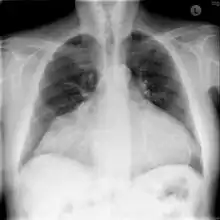

Chest X-ray: unusual heart contour due to a heterotopic heart transplantation. There is a native heart with a left ventricular aneurysm on the left, and the slightly smaller donor heart next to it on the right. -